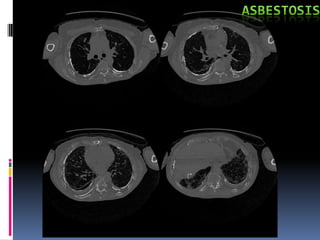

Radiografía:

• Opacidades irregulares pequeñas predominantes en los 2/3 inf

de los campos pulmonares.

•Ocasionalmente opacidades redondeadas pequeñas, con

engrosamiento      pleural,  circunscrito   o   difuso    con

calcificaciones, reduciendo la capacidad vital y los famosos

“dedos hipocráticos”

Antecedente de exposición continua.

Estertores basales inspiratorios, cianosis,

dificultad respiratoria, callosidades, prurito,

Rx (placas pleurales), Espirometría: Patrón

restrictivo, TAC, histopatología, * Biopsia.